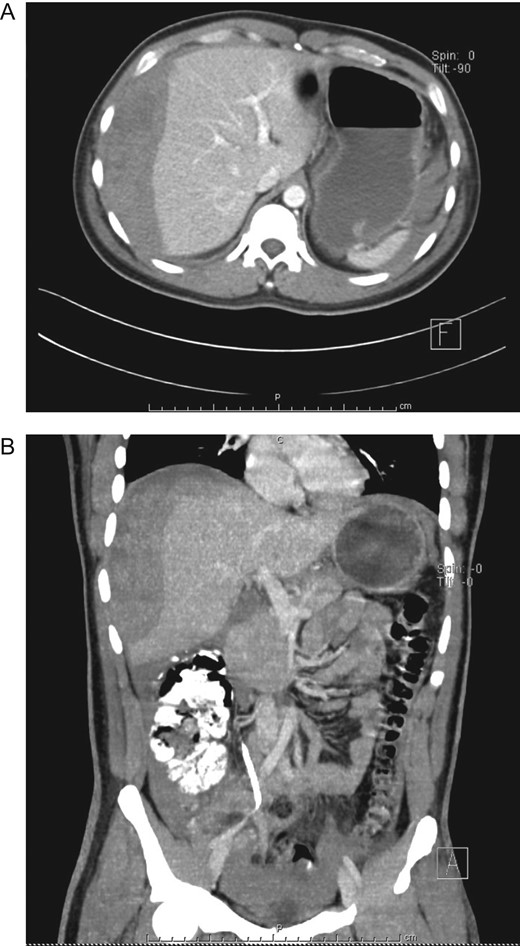

After adequate resuscitation and analgesia, his pressure and vital signs were stabilized, laboratory exams did not reveal leukocytosis or anemia however his hemoglobin (Hb) level decreased 4 points from 18 to 14 g/dl. He was admitted for close surveillance and under continuous monitoring. During hospitalization, the patient remained stable without tachycardia or episodes of hypotension, his urinary output was normal and his pain disappeared. However, 48 h after admittance, a new CBC revealed a Hb of 10 g/dl, a new CT was performed and the liver hematoma had grown ~50% (Fig. 3A and B), yet as the patient remained stable, non-operative management of his liver hematoma was decided.

(A) Contrast-enhanced CT, subcapsular liver hematoma 48 h after admittance. (B) Contrast-enhanced CT, the liver hematoma had grown ~50%.